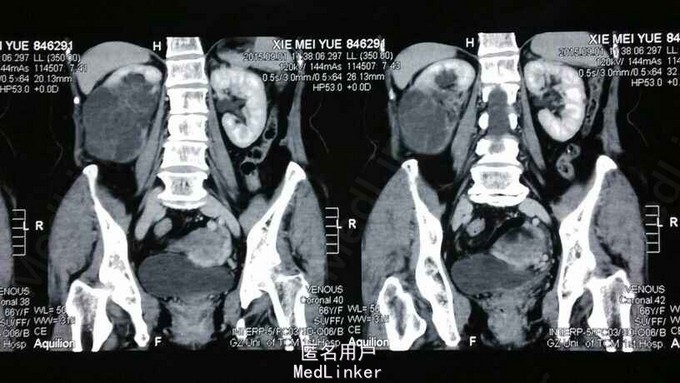

老年女性,67岁,因发现右肾囊性占位3周入院。

查体:双侧肾区无膨隆,双侧肾区无叩压痛,未触及肿块;右侧腰部可见陈旧性手术疤痕。肾功能检查提示左肾血流灌注正常,右肾血流灌注减低;右肾功能中度受损,总肾功能轻度受损,左肾不完全代偿。CT提示右肾下极前部见8.5x11x12cm类圆形不均匀低密度肿物,内见多发分房状囊样低密度影及不规则斑片组织状软组织密度影,增强扫面无明显强化,右肾多发囊性肾癌与多发囊性肾瘤鉴别。

诊断:右肾囊性肿物性质待查,双肾囊肿 治疗:给予经腹腔镜切除右肾。

随访:肿物病理未出,术后患者生命体征平稳。 讨论:肾囊肿常见,但是长这么大,组织切开时可见蜂巢状外观,有液体溅出,这样的肿瘤却不多见。请问这可能是什么肿瘤呢?